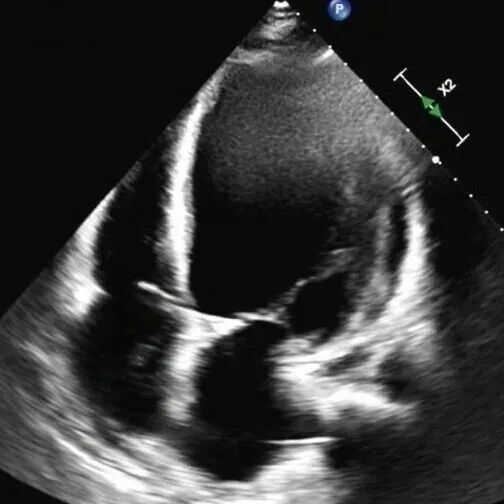

61岁的李先生(化名)三年前就偶尔出现胸闷乏力,一个月前,他因夜间无法平卧、呼吸极度困难,被紧急送往beat365唯一官方网站第一附属医院(第一临床医学院)心脏重症监护室。通过系统检查,李先生左室舒张末期内径102mm(男性的正常值≤55mm),主动脉根部瘤样扩张63mm(正常≤35mm),左室射血分数仅21.83%(正常≥50%),心功能IV级(NYHA分级),主动脉瓣重度关闭不全,二尖瓣轻-中度关闭不全,最终确诊为终末期心衰,巨大心脏,主动脉根部瘤样扩张,随时发生主动脉夹层/主动脉破裂危及生命,此外主动脉瓣重度关闭不严,心功能极差,心脏随时可能“停摆”。

术前心脏超声